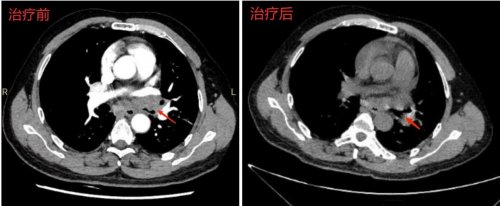

患者男性,50岁,确诊晚期肺腺癌(ALK阳性)8月余,经靶向治疗后病灶曾有吸收好转,4月18日因气喘进行性加重,再次收治市二院呼吸与危重症医学科综合病区。复查胸部CT和气管镜显示左肺门肿块突入左主支气管及左上、下叶支气管管腔,导致左主支气管管腔重度狭窄。如不积极给予处理,左主支气管一旦完全阻塞后,发生左全肺不张将加重患者呼吸困难,给后续治疗增加很大风险。

经呼吸介入团队、麻醉科多学科会诊和术前评估,建议采用经硬镜激光消融治疗。与电凝、圈套、APC比较,激光治疗对于中心气道腔内宽基底较大肿瘤组织具有消融效率高,操作时间短的优势,术中应瞄准气管解剖结构,避免出现大出血、穿孔、气道着火等风险,术前认真学习和观摩泌尿外科应用激光治疗前列腺增生手术。

4月29日,在麻醉科、泌尿外科、手术室和内镜中心护理团队的配合下,全麻状态下硬质支气管镜和奥林巴斯1T150软镜结合进入左主支气管中段,左主支气管远端可见宽基底新生物近乎完全阻塞左主支气管。在泌尿外科副主任医师王二鹏的现场指导下,全麻状态下硬质支气管镜植入左主支气管中段,左主支气管远端可见宽基底新生物近乎完全阻塞左主支气管。启动钬激光,选择钬激光功率自 20-40W逐渐升高对肿瘤组织进行消融切割,协同应用活检钳清理。经过30分钟激光消融和清理治疗,突入到左主支气管及左、下叶管腔内的肿瘤组织基本清理干净,管腔通畅。术后患者气喘症状明显缓解。